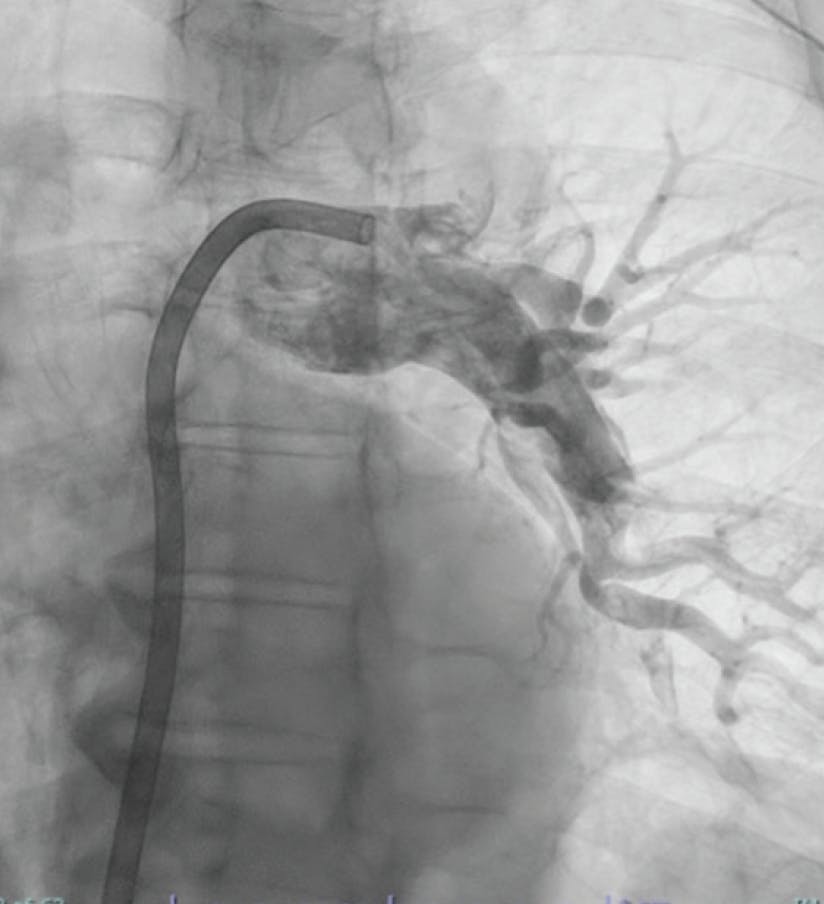

A woman in her early 70s with a medical history of hypertension, hyperlipidemia, peripheral artery disease, type 2 diabetes mellitus, and a recent diagnosis of stage IV pancreatic cancer presented to the emergency department with hour-long chest pain and dyspnea, as well as cramping in the right calf. She underwent the CT pulmonary embolism (PE) protocol, which showed significant clot burden with a saddle PE extending into the bilateral main pulmonary arteries (PAs) (Figure 1 and Figure 2). Her lactate level was 8.2 mmol/L. She was started on a heparin drip and had evidence of hypoxia that required 3 L of nasal cannula. Initial vitals recorded a blood pressure of 117/82 mm Hg, heart rate of 96 bpm, SpO2 of 87%, and respiratory rate of 31 breaths per minute. There was evidence of right heart strain with a right ventricular/left ventricular (RV/LV) ratio of 1.4 by CT, as well as a high PE Severity Index. Given the large clot burden, marginal hemodynamics, and hypoxia, we decided to move forward with CAVT with Lightning Flash 2.0.

Figure 1. Initial angiogram of the left lobe.

INTERVENTION

After achieving wire access, the Lightning Flash 2.0 was inserted. While in “Gallop Mode,” the saddle clot burden and subsequently the left and right main PAs were aspirated. Once the algorithm returned to “Sampling Mode,” aspiration was turned off and angiograms were obtained to assess the progress. After 5 minutes of aspiration, reperfusion of the main PAs and distal branches was achieved (Figure 3, Figure 4, and Figure 5), with improvement in the patient’s vital signs and no device-related complications.